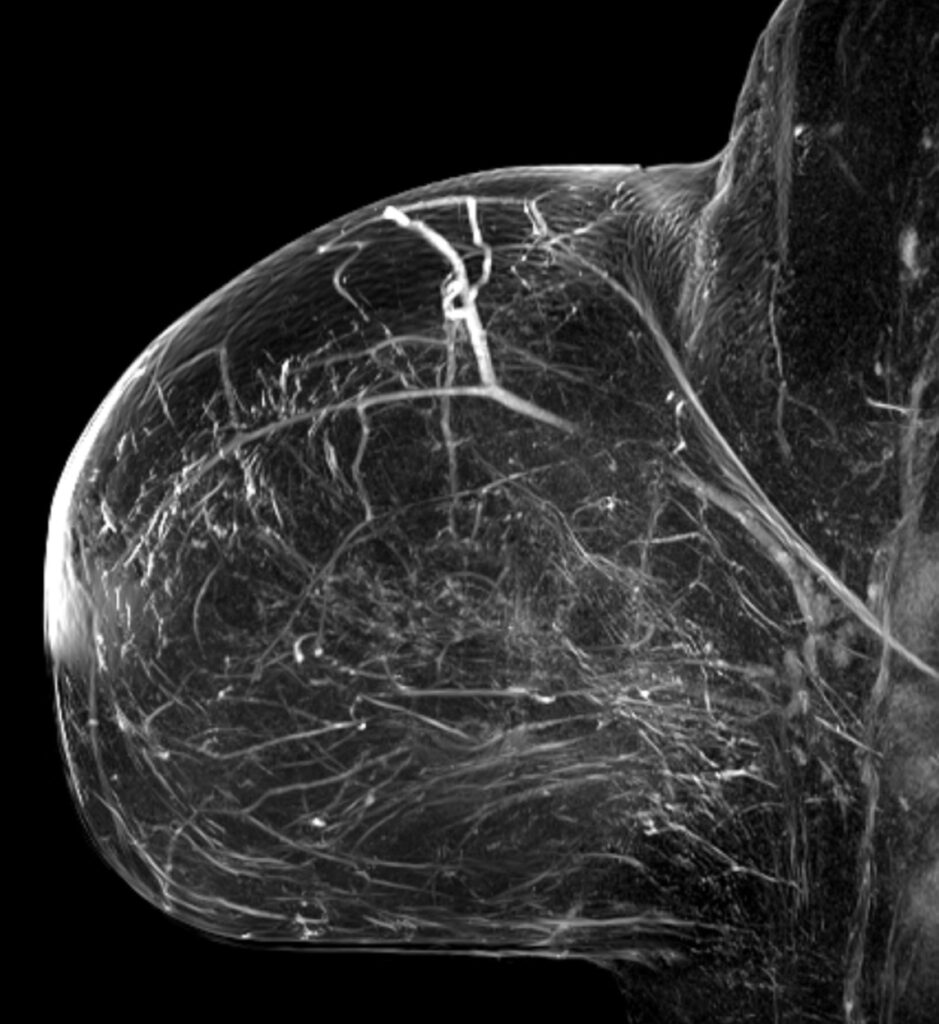

- Beurteilung der Tumorausbreitung: Die MRT der Brust hilft dabei, die Ausdehnung eines Tumors zu bestimmen.

- Beurteilung von Brustimplantaten: Eine Brust MRT kann auch Defekte in Brustimplantaten (z. B. Risse oder Undichtigkeiten) nachweisen.